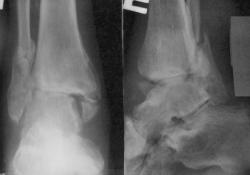

2. Следом приходит второй.

В процессе лечения 6 месяцев назад

В деревне запил, показался только сегодня

Ваше мнение о наличии консолидации?

1. Консолидации конечно, такой как должно, нет. Вопрос1- почему не оперирован? Вопрос2-для себя, это последствия ДТП (ведь имееется "бампер-перелом")?

2. Сформированы "псевдоатрозы", наличиствует подвывих стопы наружу...пусть пьет дальше...авось "срастется"....